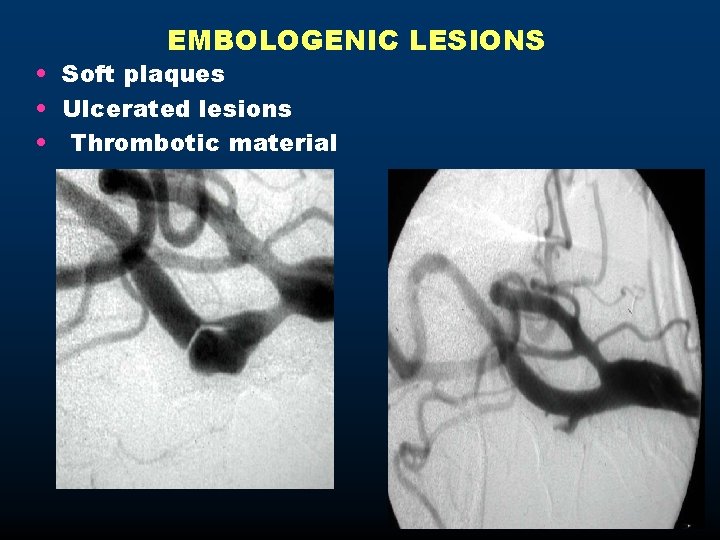

EMBOLΟGENIC LESIONS • Soft plaques • Ulcerated lesions • Thrombotic material